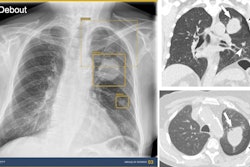

DDR is an emerging imaging technique that uses a pulsed x-ray source to acquire a series of radiographs at six to 15 frames per second. These images are then processed to visualize joints in motion. The technology has been applied to several thoracic and musculoskeletal imaging applications and notably has previously been used to visualize the SHR.

In this study, the goal was to develop a DL algorithm that can automatically determine the SHR, which normally requires complex and time-consuming manual calculations by clinicians and thus is rarely performed in routine clinical cases, he said.

The prototype DL algorithm was trained on 447 images from 267 cases to recognize the humerus and scapula positions, calculate the required scapulothoracic and glenohumeral angles, and thus determine the SHR across the complete range of abduction.

The performance of the algorithm was then evaluated by comparing its measurements with manual human reader measurements on a unique data set of 73 shoulder exams (23 normal controls, 41 rotator cuff tears, and nine adhesive capsulitis cases), with the AI and human measurements compared using intra class correlations (ICC).